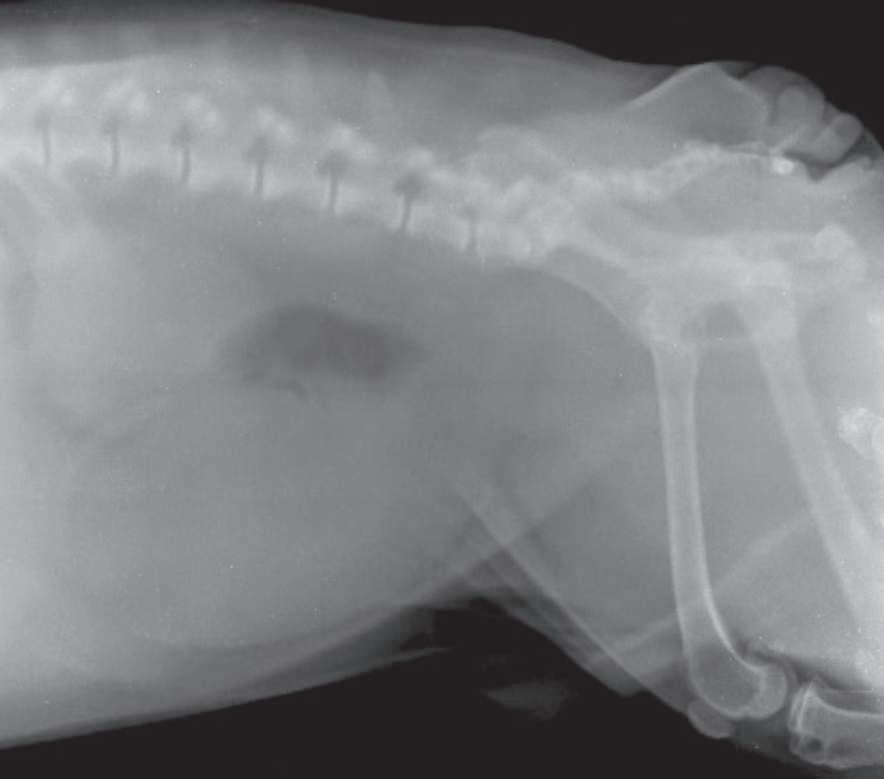

Imagen radiográfica en proyección lateral izquierda derecha, en la cual se aprecia vejiga plétora, con cambios de densidad en la luz vesical correspondientes a zonas aparentemente nodulares que corresponden a irregularidades en el contenido vesical como la presencia de urolitos (p. 81).